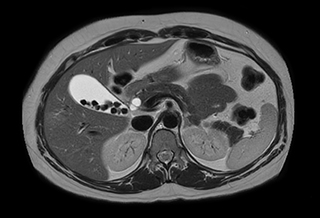

Performed on Ingenia Ambition. FOV 430 mm, voxels 1.3 x 1.3 x3.0 mm, 130 slices, Breath hold 16.6 sec

Using mDIXON provides excellent fat saturation uniformity. No artifacts seen at the edges in these images, while these were quite commonly seen with eTHRIVE on our previous system. Note also the high resolution.